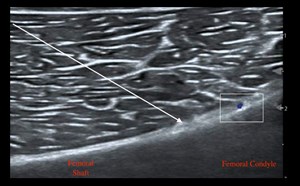

By Vivek S. Tayal, MD, FACEP and Jim Villareal, MD, FACEP The ECRI Institute, a nonprofit organization that evaluates health care technology, published a report of the “Top 10 Medical Technology Hazar...